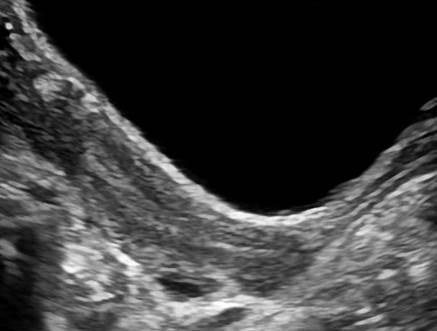

Dị dạng tử cung

Dị dạng tử cung - Ảnh 2

» Thông tin: Nữ giới – 14 tuổi.

» Lâm sàng: Kiểm tra sức khỏe.

# Tử cung có vách ngăn (Septate uterus).